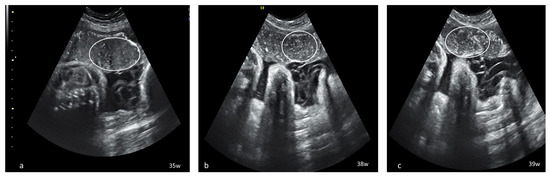

Dynamic evaluation of the placental morphology revealed what seems to be a particular pattern of placental remodeling starting from 30 WG towards term following SARS-CoV-2 infection during pregnancy. We noted the occurrence of dispersed hyperechoic foci, without posterior acoustic shadowing, scattered across the placenta, increasing in number and size with consecutive examinations, creating a “starry sky” appearance similar to the sonographic pattern described in acute hepatitis (Figure 1) [22]. Consequently, these foci conflate to form interlobular, chandelier-like, comma-shaped indentations. Later, lesions organize to form a consistent, chalky conglomerate along the entire basal plate, a “white line”, with bolded edges towards the chorionic plate forming white angles (Figure 2). Placental changes mimic the physiologic aging process but occur earlier in gestation; echo-dense foci are more widespread and organize in a short period to form the echoic white line.

Figure 1.

Serial placental ultrasound images at 35 WG, 38 WG and 39 WG, of a nullipara with confirmed SARS-CoV-2 infection at 33 WG (a) hyperechoic foci scattered across the placental surface; (b,c) increasingly denser hyperechoic foci creating a “starry sky” placental pattern (circle).